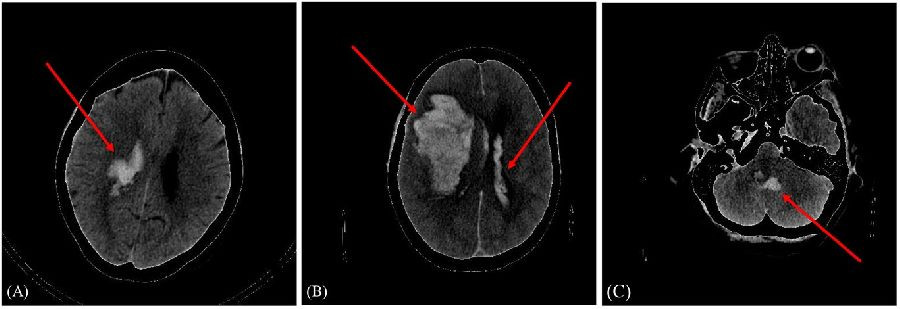

Investigadores del Instituto de Física de Cantabria (IFCA) han participado en la creación de un modelo capaz de predecir el pronóstico, favorable o no, de un paciente tras sufrir una hemorragia intracraneal.

Hasta ahora existían varios modelos de predicción para la detección de la hemorragia cerebral. Lo novedoso en este caso es que se presenta un modelo de aprendizaje profundo que predice el pronóstico de la enfermedad, es decir, si el paciente evolucionará favorablemente o no.

"Incluimos en el estudio a 262 pacientes de Cantabria que llegaban al servicio de urgencias de Valdecilla con sospechas de hemorragia intracraneal y con las imágenes de los distintos TAC cerebrales y sus datos clínicos, entrenamos un modelo personalizado para poder clasificar a los pacientes en mal pronóstico y buen pronóstico, utilizando un modelo híbrido", ha explicado Amaia Pérez.

El modelo se conoce como híbrido porque incluye dos grupos de datos: las imágenes del TAC y datos de cada paciente, y, por tanto, el rendimiento de la red mejora, "a más datos, mejores predicciones". Esos datos se obtienen de información personal, como la edad, sexo, si el paciente es fumador o consumidor de alcohol habitual o si tiene antecedentes médicos, entre otros.